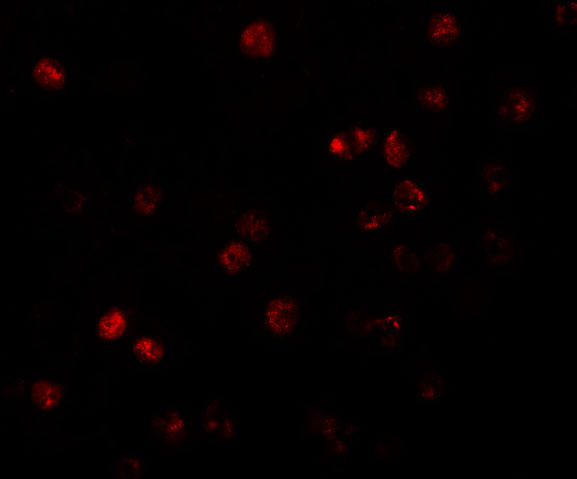

Facts about Probable phospholipid-transporting ATPase IF.

Involved in regulation of sensitivity to cisplatin; may give rise to secretory vesicle transport of cisplatin from Golgi to plasma membrane. .

Recycling endosome membrane; Multi-pass membrane protein. Early endosome. Endoplasmic reticulum. Golgi apparatus, trans-Golgi network. Exit from the endoplasmic reticulum requires the presence of TMEM30A, but not TMEM30B (PubMed:21914794). In the presence of TMEM30A, mainly located in recycling endosomes (PubMed:21914794).